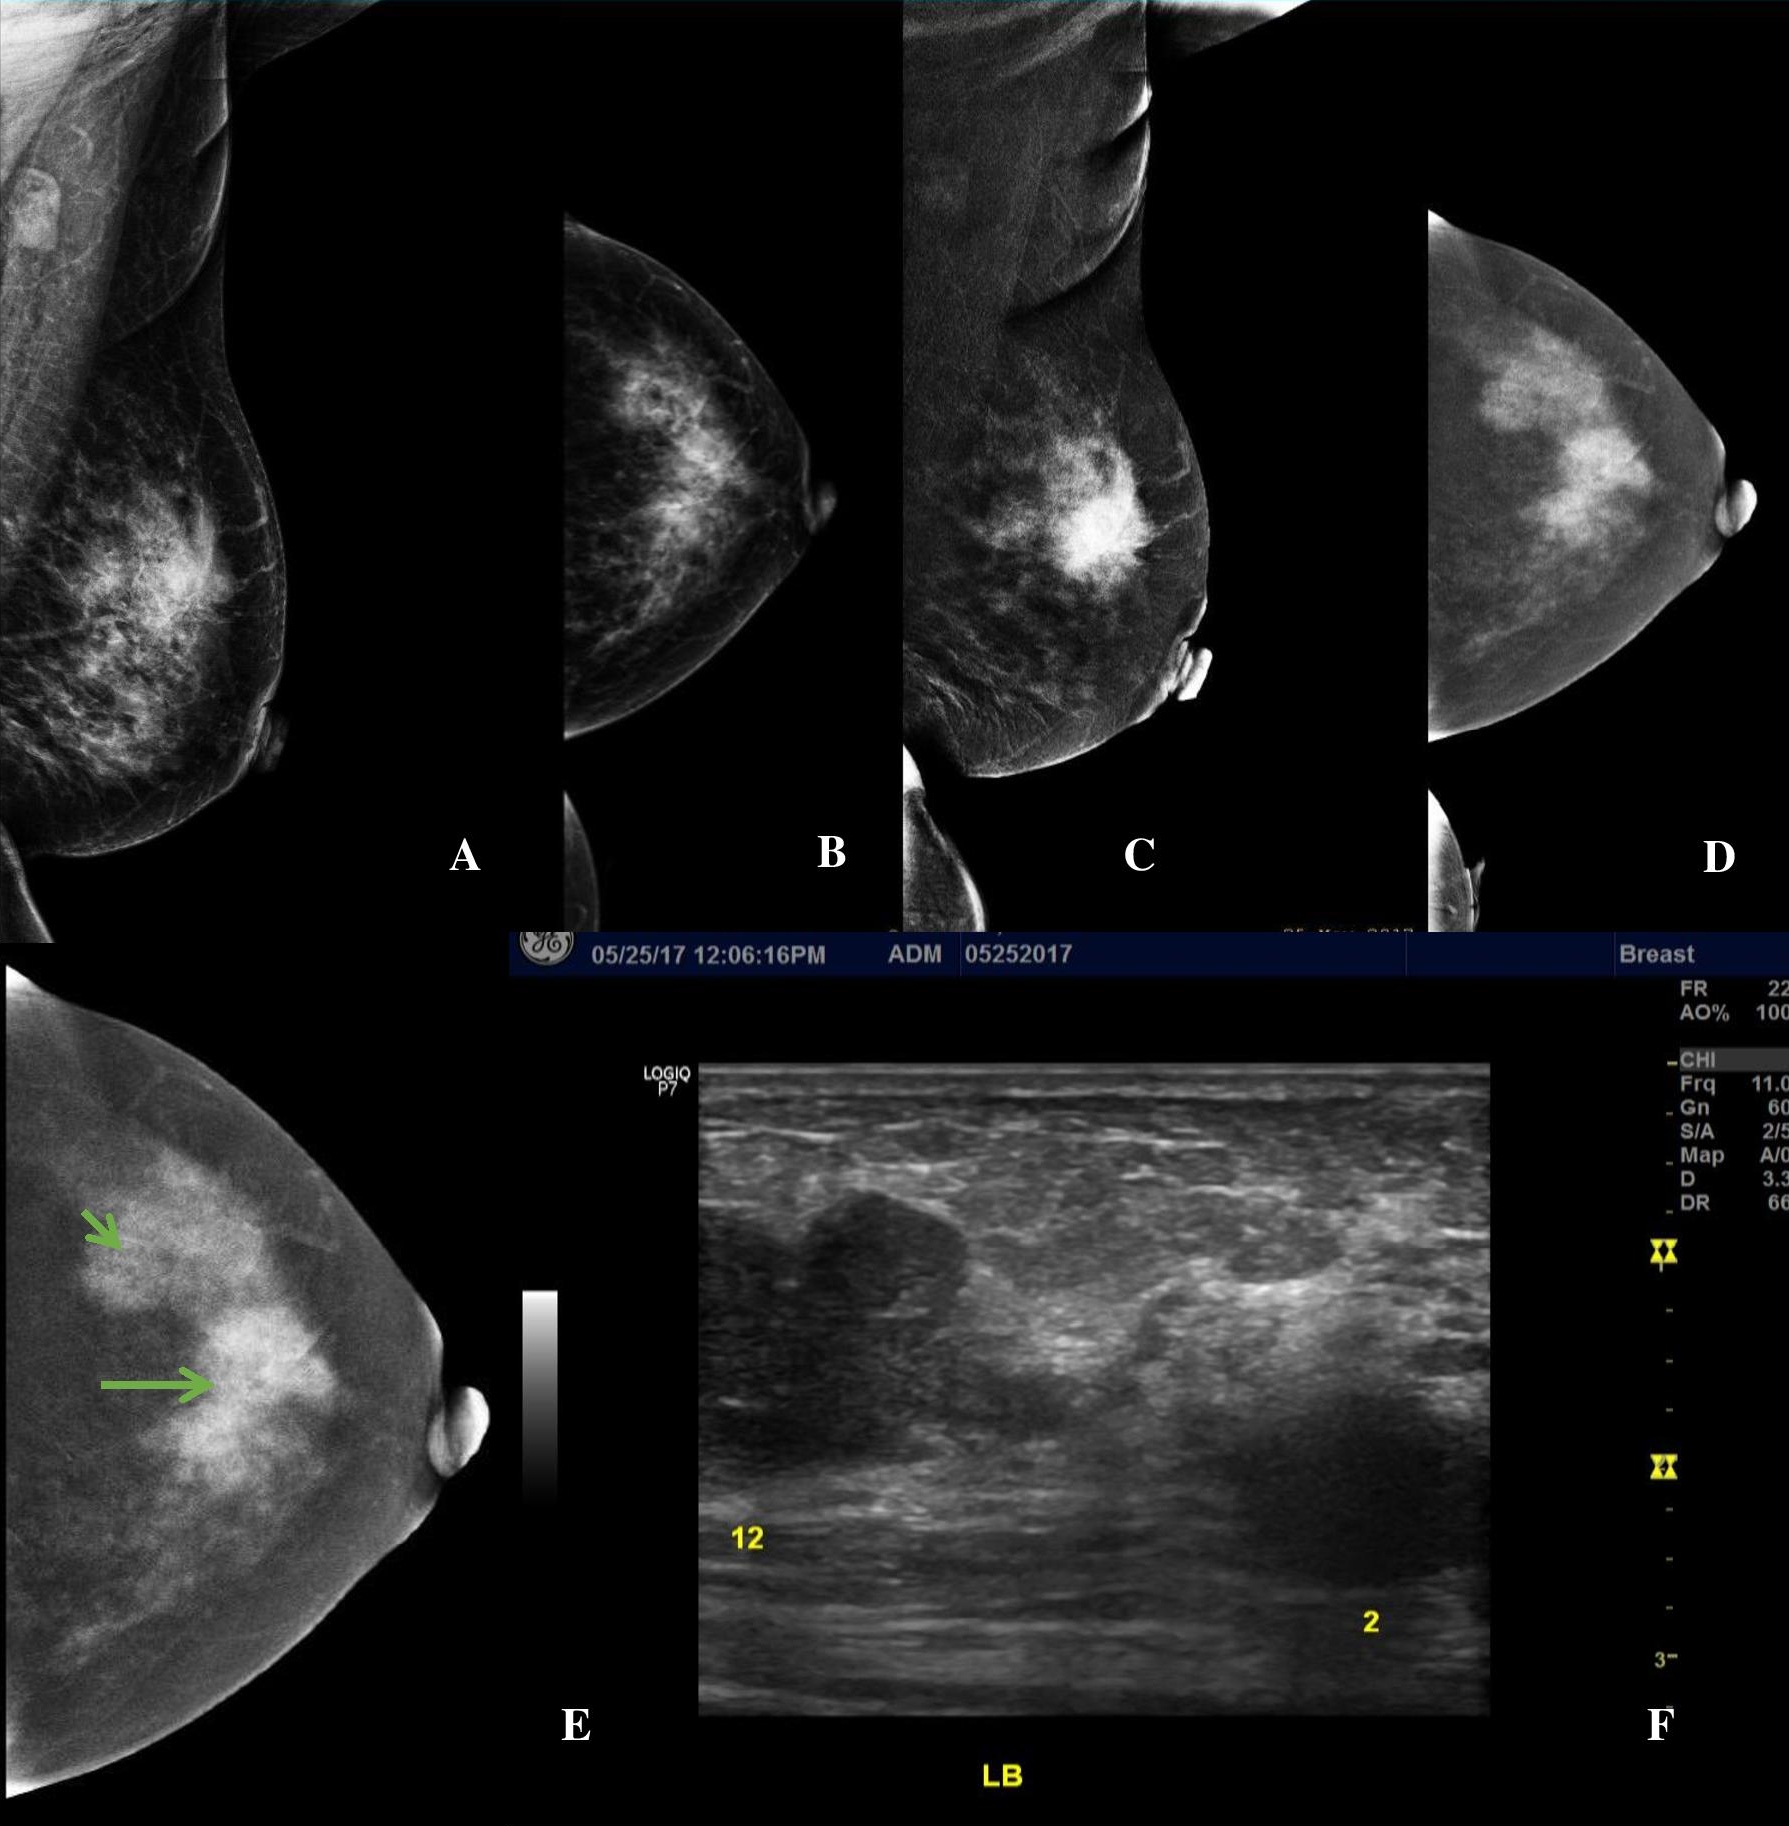

Figure 3. A 56-year-old premenopausal female presenting with a palpable left breast mass, Family history revealed she had two (2) sisters who had breast cancer in their 50’s. (A, B) LE MLO and CC views of the left breast showing heterogeneously dense breast composition. There is an irregular mass of increased density at the mid upper quadrant and a second equal density mass with partly obscured margins at the upper outer quadrant (C, D) Subtracted images (SI) in MLO and CC projections show an enhancing irregular mass at the mid upper left breast and shows the second enhancing mass with lobulations at the upper outer quadrant on a background of moderate parenchymal enhancement. (E, F) SI Image of the left CC view and the correlate ultrasound image showing multifocal breast lesions at the 12 o’clock (orange arrow) and 2 o’clock (orange arrowhead) positions.